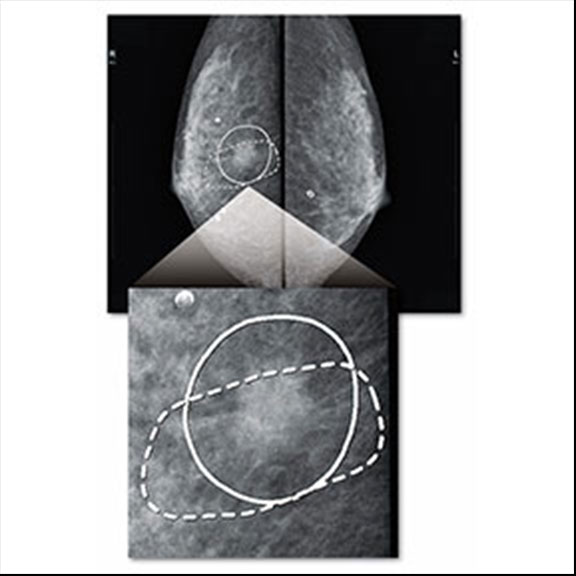

読影に優しいマーキング表示

簡単なボタン操作で、CADが検出したエリアを見やすい線で囲み表示し、画像の観察にともなうストレスの大幅な軽減に貢献します。